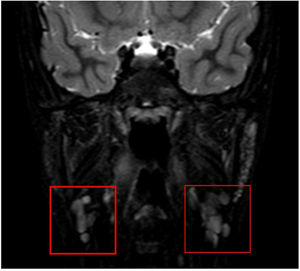

Presentamos el caso de una niña de 9 años remitida a nuestro servicio de cirugía pediátrica por una tumefacción recurrente en la base de la lengua de 5 meses de evolución. La exploración reveló una tumefacción con contenido líquido (fig. 1). El análisis histopatológico confirmó la presencia de un quiste de retención mucosa unilocular asociado a sialoadenitis crónica, atrofia acinar, ectasia ductal e infiltrado linfoplasmocitario. La resonancia magnética mostró quistes pequeños bilaterales en las glándulas sublinguales compatibles con ránulas simples y un aspecto multiquístico en las glándulas parótidas sugerente de lesiones linfoepiteliales asociadas al síndrome de Sjögren (SS) (fig. 2). La analítica reveló elevación de anticuerpos antinucleares (1:640), niveles altos de anticuerpos anti-SSA (>240U/mL) y elevación leve del factor reumatoide (32UI/mL). Otras pruebas, como la enzima convertidora de angiotensina sérica, el proteinograma, subclases de inmunoglobulina, niveles de complemento, crioglobulinas y anticuerpos anti-dsDNA, anti-SSB y anti-U1RNP, estaban dentro del rango normal. El test de Schirmer confirmó un déficit grave en la producción de lágrimas (<5mm). Posteriormente, la paciente desarrolló síndrome seco, que mejoró con tratamiento sintomático.